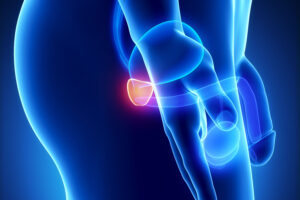

Die Prostatabiopsie

Welche Symptome können durch Erkrankungen der Vorsteherdrüse (Prostata) hervorgerufen werden? Zur Beantwortung dieser Frage unterscheidet man sinnvoller Weise drei grundsätzlich verschiedene Krankheitsbilder: den Prostatakrebs (Prostatakarzinom) die gutartige Prostatavergrößerung (‚Altmännererkrankung’, Benigne Prostatahyperplasie) und die Prostataentzündung (Prostatitis).

Allgemeines rund um die Prostata

„Moderne bildgebende Diagnostik der Prostata“, „MRT-/TRUS Fusionsbiopsie“, „Fokale Therapie des Prostatakarzinoms“, „Ergebnis der Prostatabiopsie“ usw. – in unserem Patientenratgeber beleuchten wir eine Vielzahl wichtiger, aber teilweise recht spezieller Aspekte rund um das Thema „Prostatakrebs“. Nach